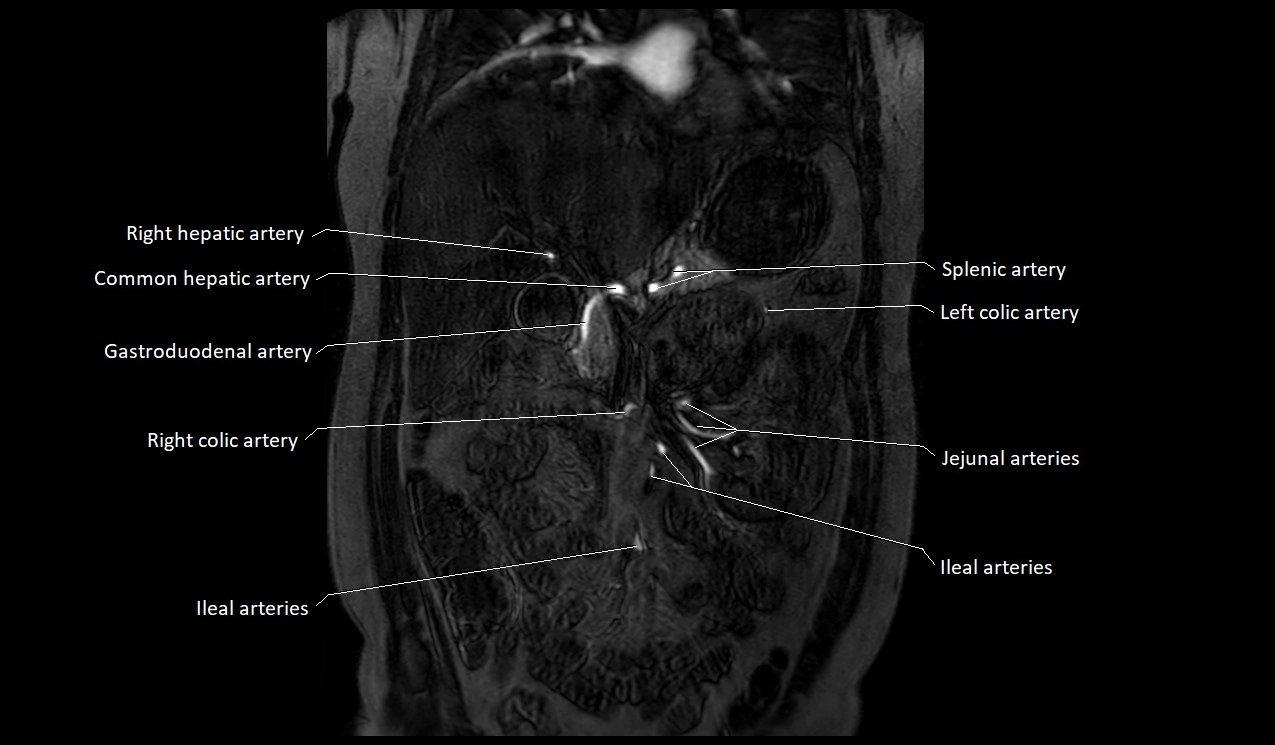

MRI Appearance

T1-weighted images:

-

Artery appears as a small linear hypointense flow void coursing over the superior pubic ramus

Seen within bright perivascular fat of pelvis

T2-weighted images:

Artery lumen is a signal void

In thrombosed or diseased variants, lumen may appear hyperintense relative to surrounding fat

STIR:

Fat suppression makes the artery more visible within pelvic fat

Helps identify perivascular edema, hematoma, or inflammatory changes

T1 Post-Gadolinium (with fat suppression):

Artery enhances brightly and homogeneously

Useful for tracing the course, anastomoses, and presence of corona mortis

Highlights arterial wall thickening or tumor encasement if present

MRA Pelvis with Gadolinium:

Clearly delineates the origin, course, and anastomoses of the accessory obturator artery

Identifies connection with inferior epigastric artery, external iliac artery, or obturator artery

Excellent for detecting vascular variants prior to surgery

Useful in mapping pelvic vasculature in trauma, tumor embolization, or preoperative planning